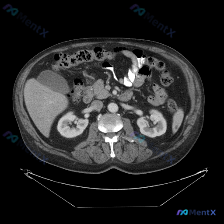

整理了一个很有警示意义的影像读片场景,特别能体现「循证影像诊断」的重要性。 先看「预设问题」与「影像事实」的冲突 预设: 临床/提问指向「图中存在脾脏病变」 影像事实(单帧增强CT): - 扫描层面:仅上腹部,显示肝右叶部分、胆囊、双肾、胰腺、血管、胃及肠管 - 强化状态:增强扫描(血管强化明显),...